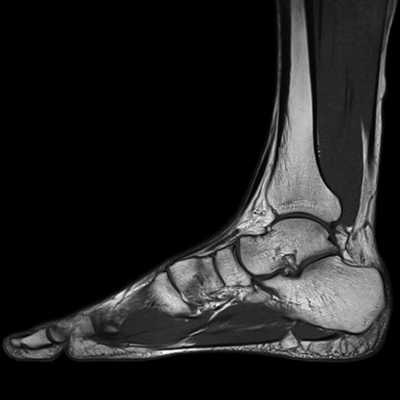

(Слева) МР-артрография в режиме Т1ВИ, коронарный срез, пациент 25 лет: визуализируется обширное повреждение суставного хряща подтаранного сустава вследствие перелома пяточной кости.

(Справа) МР-артрография в режиме Т1 ВИ, сагиттальный срез: спереди видны участки неизмененного хряща, а сзади - выраженное его истончение. В голеностопном суставе отмечаются признаки остеоартроза. У этого пациента подтаранный сустав сообщается с полостью голеностопного сустава. Лечение заключалось в артродезе обоих суставов.